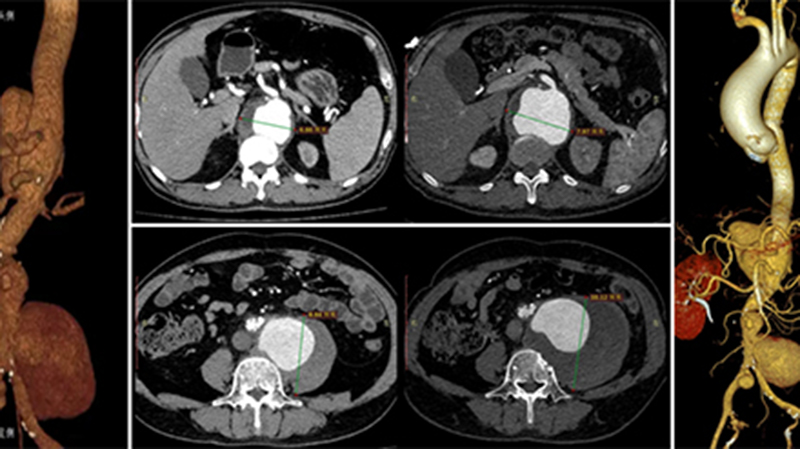

近期,山东第一医科大学附属省立医院(山东省立医院)进行了2023年度技术创新奖和重大抢救奖评选。为让社会大众更深入、更精准地认识医院优秀科室,展现医院近年来疑难复杂疾病救治能力和医疗技术水平的进步,让患者及家属享受到更加优质、高效、快捷的诊疗服务,医院将陆续推送相关获奖案例。51岁患者李先生因“腰腹痛5月,间断发热、乏力、多汗4月”转入山东第一医科大学附属省立医院(山东省立医院)治疗。李先生既往高血压病史10年…